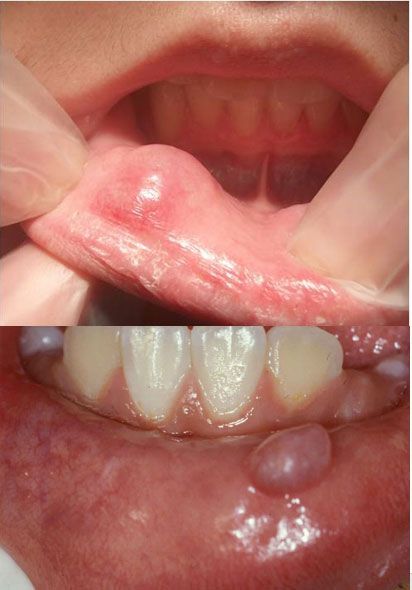

Mucocele en labio

Se trata de una lesión benigna muy común que se origina debajo de la acumulación de saliva de los tejidos blandos del labio. Se produce, entre otras cosas, por morderse repetidamente el labio, recibir un golpe o cualquier otro tipo de trauma.

Su tratamiento se da mediante la extirpación quirúrgica, en caso de que la lesión sea dolorosa o de gran tamaño.